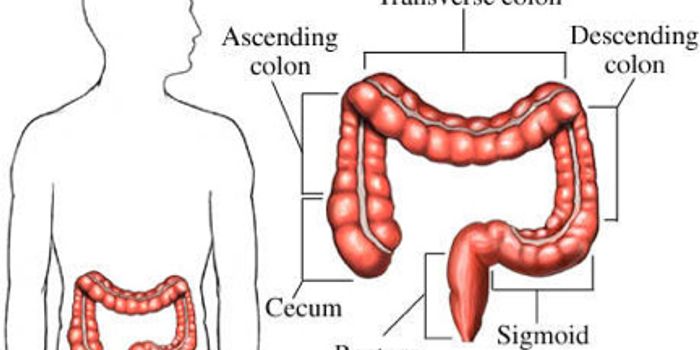

JUL 13, 2015CancerHow important is screening for colon cancer? It's very important, according to a study in the July issue of GIE: Gastroi ...

JUL 26, 2016CancerColon cancer is the third most common non-skin cancer type in the U.S. Now researchers say they have gained a huge advan ...

AUG 19, 2021CancerColorectal cancer (CRC) is the third most diagnosed type of cancer in both men and women in the United States and CRC in ...

FEB 09, 2023CancerColorectal cancer (CRC) can develop in any part of the colon, the large intestine, or the rectum, the area of the body c ...

MAY 20, 2016CancerLocation, location, location! Researchers have found that colorectal patients whose tumor is located on the left side of ...